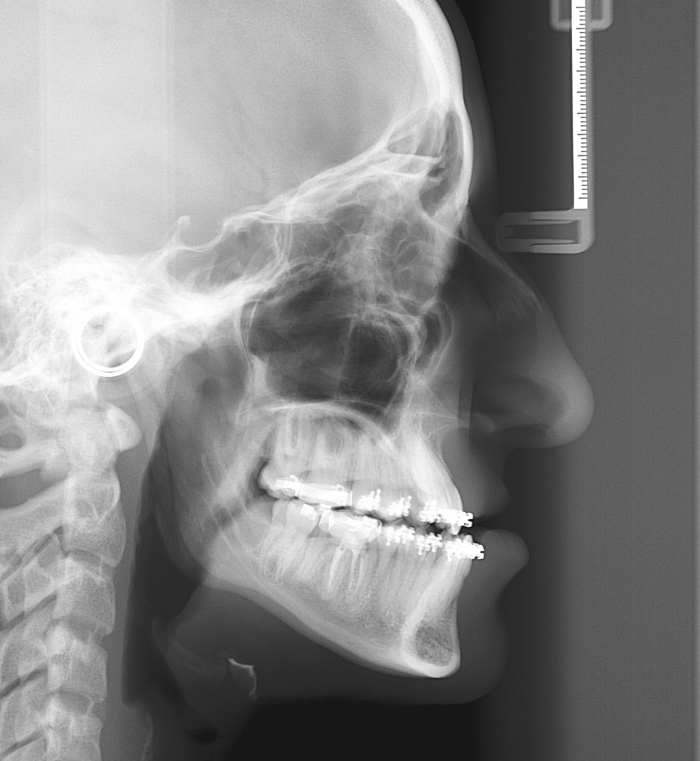

Telerradiografia perfil inicial - Clínica Cliniface

Telerradiografia perfil inicial